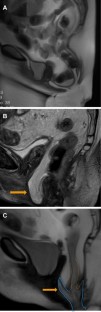

Fig. 3